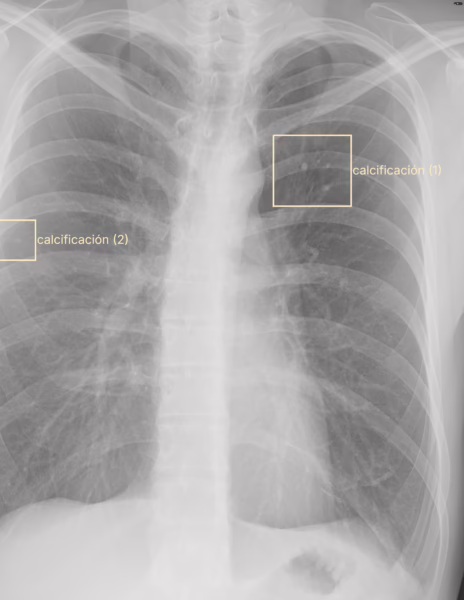

Los pulmones son simétricos y radiolucidos, de manera bilateral en los tercios medio se observa calcificaciones menores a 0.5 cm. No se identifican patrones radiopacos o radiolucidos por este método de estudio. El diafragma conserva la convexidad. Los ángulos diafragmáticos conservan la profundidad.La tráquea se encuentra central con presencia de aire. El arco aórtico se encuentra normal. La silueta cardiaca es homogénea.Los hilios son de diámetro normal y situación anatómica normal.

IMPRESIÓN DIAGNOSTICA:

Calcificaciones pulmonares bilaterales